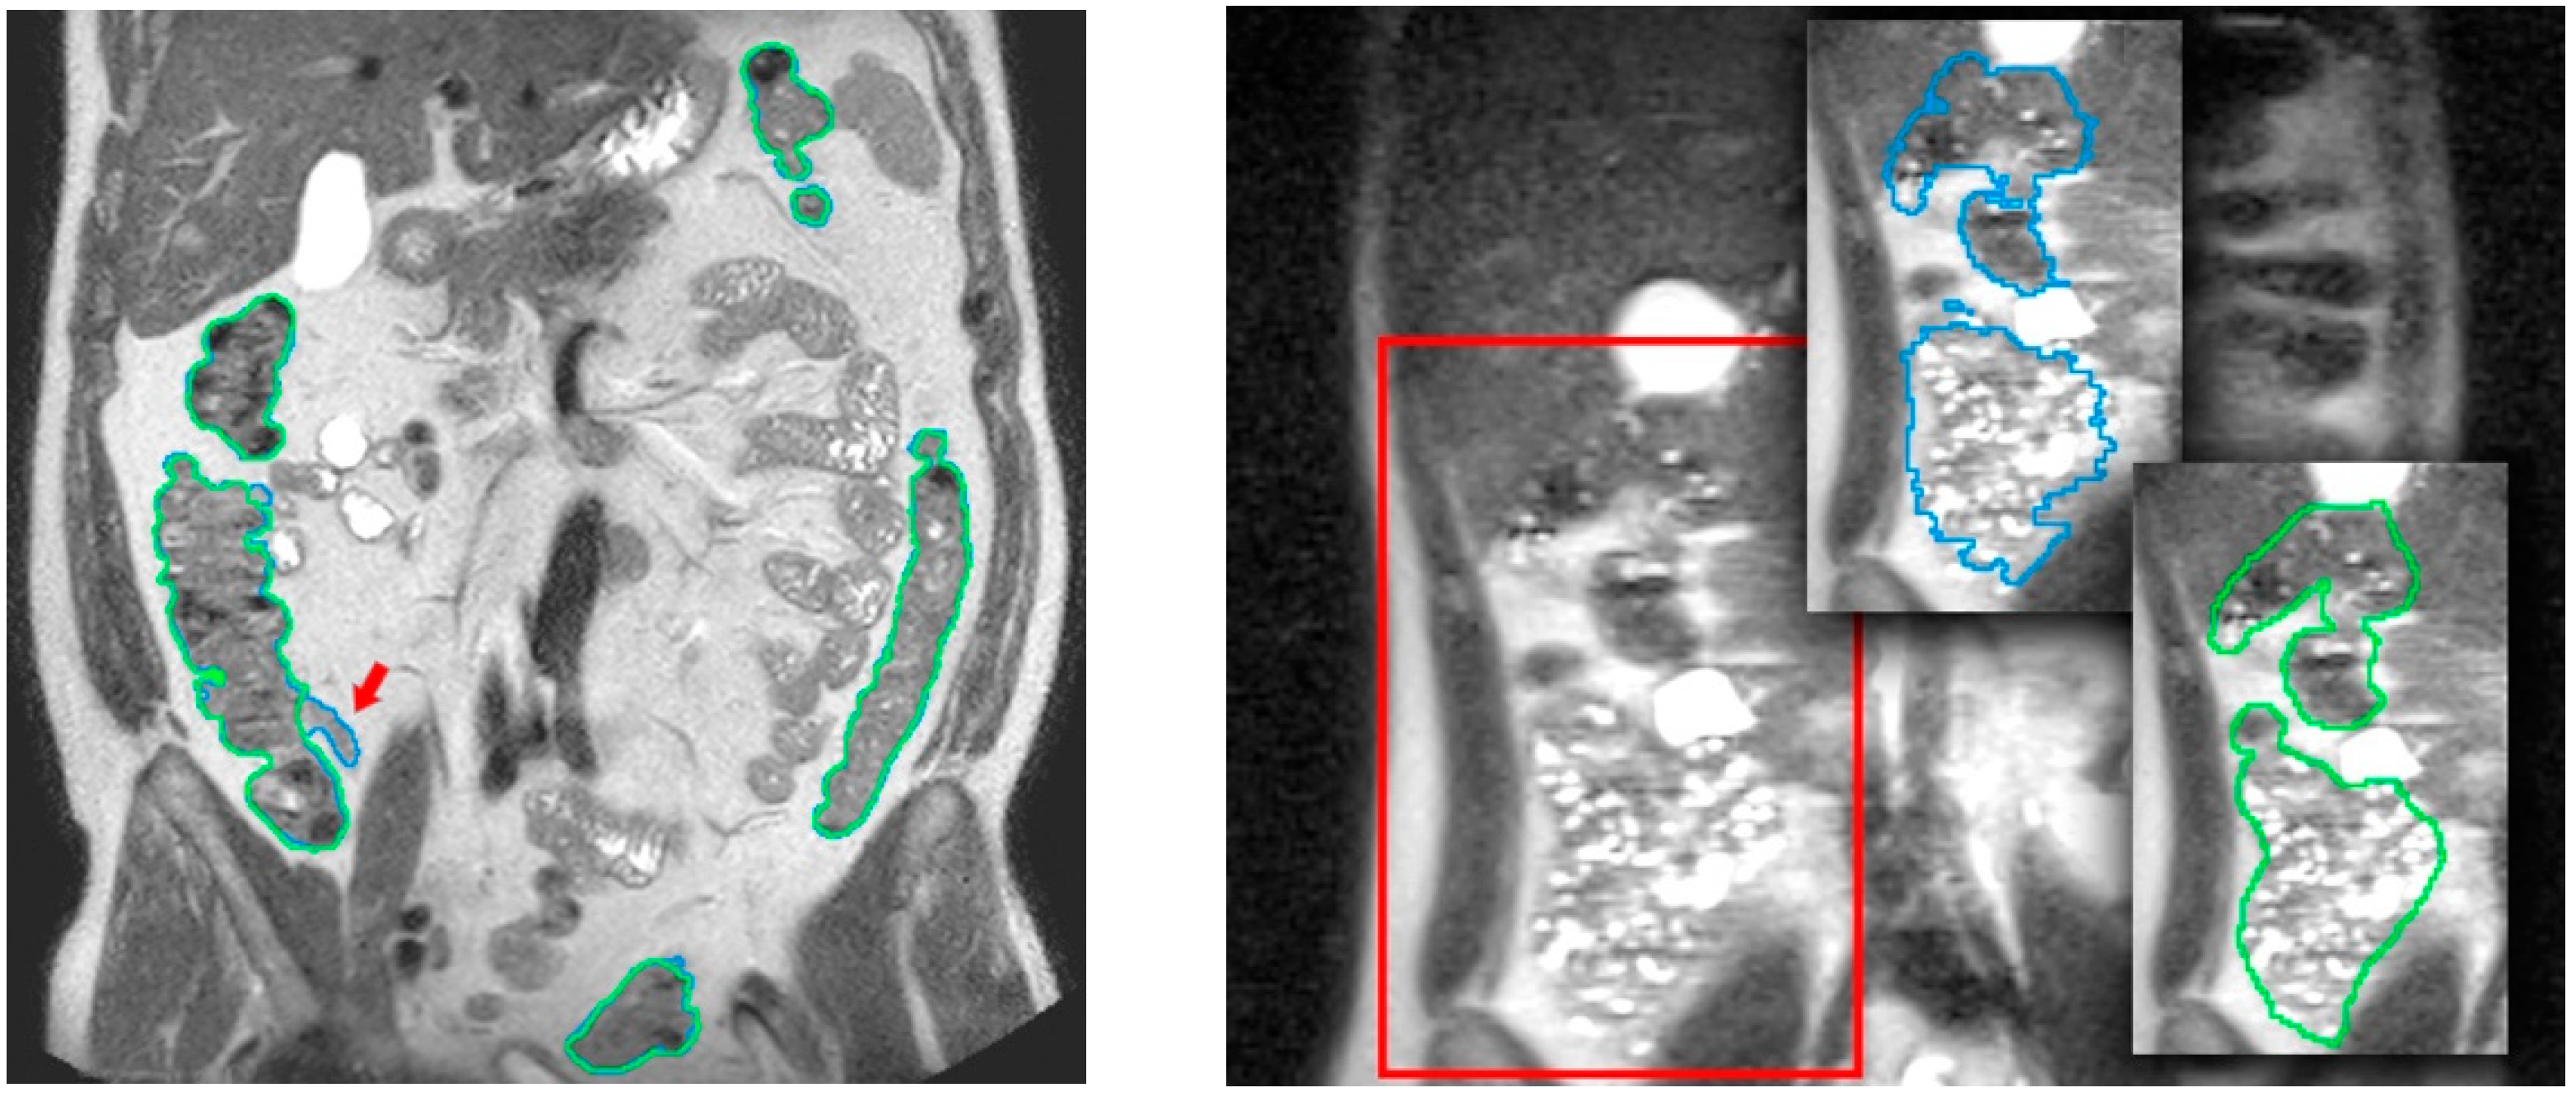

Figure 4.

Comparison of segmentation results (in blue) with a ground truth manual colon segmentation (in green) in T2 images. In the left image, the red arrow marks a small ileum region wrongly assigned to colon by the automatic algorithm. In the right image, a highly challenging area even for the specialists (outlined in red) is shown. Courtesy of [7].

The validation of the colon segmentation from T2 images was presented in [7]. In total, 52 scans were used in the accuracy experiment: 30 scans from 15 healthy participants (8 women, 7 men) and 22 scans from 11 patients (8 women, 3 men) with irritable bowel syndrome (IBS); participants had a normal body mass index or were overweight (body mass index between 18.5 and 29.9 Kg/m2), i.e., no underweight or obese subjects were included. The assessment of the algorithm accuracy was performed by comparing the segmentation results to the ground truth (specialist manual segmentation) using the dice similarity coefficient (DSC). The achieved accuracy was (µDSC = 0.85, σDSC = 0.06), demonstrating its suitability for clinical usage. Figure 4 compares results of the colon segmentation computed by the algorithm with respect to a ground truth segmentation manually performed by the medical expert. In the left image, the medical expert did not realize that a small ileum region had been wrongly identified as colon by the segmentation algorithm. This misclassification was probably due to a similar pixel intensity in both the ileum and the adjacent colon, which made it very difficult to identify the colon in that area. As explained in Section 3.2, a simultaneous visualization of the T1-FS images could have helped him to fix this wrong identification. From the point of view of performance, the average execution times (in minutes) for all the volumes involved in the experiment were in the range 5.7 ± 1.16 min, with a maximum peak of 8.5 min, and the memory usage was below 2.5 GB. Focusing on the usability of the process, the experiments demonstrated that this approach could be considered as low demanding in terms of user time (on average 5′ of usage time). Compared to the initial approach presented in [12], usage times have been reduced by 80%.

Regarding the validation of the colon segmentation in T1-FS images, the algorithm accuracy was evaluated by comparing the automatic segmentation results to manual segmentations of the colonic fecal content (taken as ground truth) performed by the specialist (in [15] the validation experiments were presented). Note that the specialist only segmented the fecal content because the complete segmentation was too demanding and almost impossible in areas where no fecal content was presented (areas with gas).

In total, 90 scans obtained from 35 healthy volunteers (8 women, 27 men; 20–28 Kg/m2 body mass index range) were used. The quantitative validation metric, named R, was defined as the percentage of ground truth fecal content inside the colon segmentation result. The achieved accuracy was (μR = 96.2%, σR = 4.2), demonstrating its viability for clinical usage (see Figure 5). The mean execution time was 9 min without any human intervention.